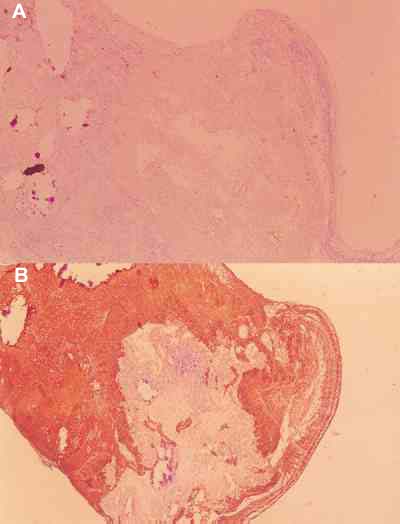

Retinoblastoma Exofítico:

el crecimiento se realiza hacia el espacio

subretinal y desprende la retina (figuras 2A y 2B).

Figura 2. A) Aspecto macroscópico de un retinoblastoma exofítico

con desprendimiento total de retina. B) Confirmación histológica de este

patrón. GFAP (60x).